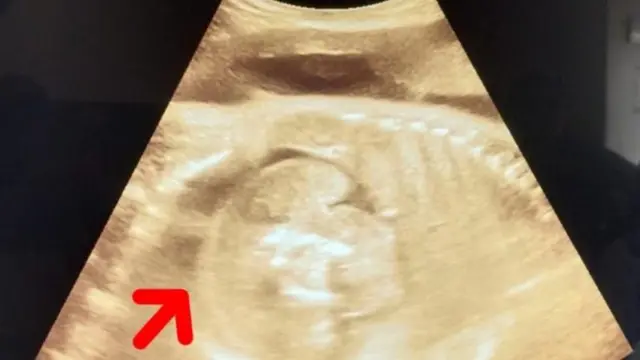

મહારાષ્ટ્રના બુલઢાણા જિલ્લામાં એક મહિલાના પેટમાં બાળક અને તેના પેટમાં પણ એક બાળક જોવા મળ્યું.

બુલઢાણા જિલ્લાની એક ગર્ભવતી મહિલા સોનોગ્રાફી માટે સરકારી હૉસ્પિટલમાં ગઈ હતી, ત્યારે આ ઘટના ઉજાગર થઈ.

સોનોગ્રાફી કર્યા પછી સંબંધિત મહિલાના પેટમાં બાળક હતું અને બાળકના પેટમાં પણ બાળક જોવા મળ્યું.

તેની તપાસ કર્યા પછી ખબર પડી કે, મહિલાના પેટમાં જે ભ્રૂણ છે તેમાં પણ એક ભ્રૂણ દેખાય છે.

એટલે સુધી કે, જ્યારે ડૉક્ટરો અને નિષ્ણાતોની ટીમે ફરી વખત સોનોગ્રાફી કરી ત્યારે બાળકના પેટમાં ગર્ભ સ્પષ્ટ દેખાતો હતો.